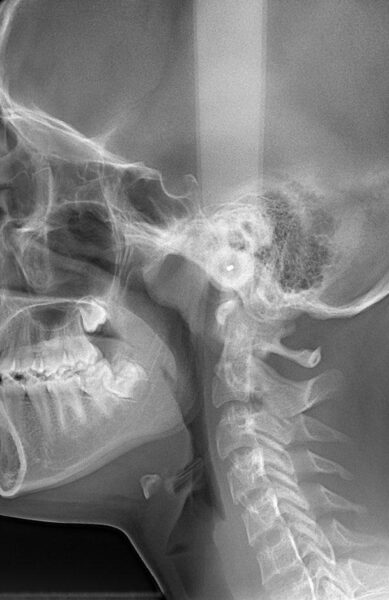

مرکز تخصصی رادیولوژی دهان، فک و صورت دکتر یاسر صافی ، ارائه کلیه خدمات رادیوگرافی اعم از پانورکس ، رادیوگرافی سفالوگرام ، Cone Beam Computed Tomography (CBCT) ، رادیوگرافی پری اپیکال ، رادیوگرافی بایت وینگ ، رادیوگرافی واترز ، رادیوگرافی تعیین سن استخوانی ، سیالوگرافی ، رادیوگرافی مفصل تمپور و مندیبولر، انجام خدمات سونوگرافی نسج نرم و غدد بزاقی و فوتوگرافی برای عموم مردم ، تخصصی ترین مرکز رادیولوژی تهران با ارایه خدمات تصویربرداری در محل

انواع رادیوگرافیهای تخصصی دهان، فک و صورت با دستگاههای مدرن و کمترین دوز تابشی

تصاویری از محیط داخلی مرکز تخصصی رادیولوژی دهان،فک و صورت دکتر یاسر صافی و نمونه تصاویر خدمات ارایه شده